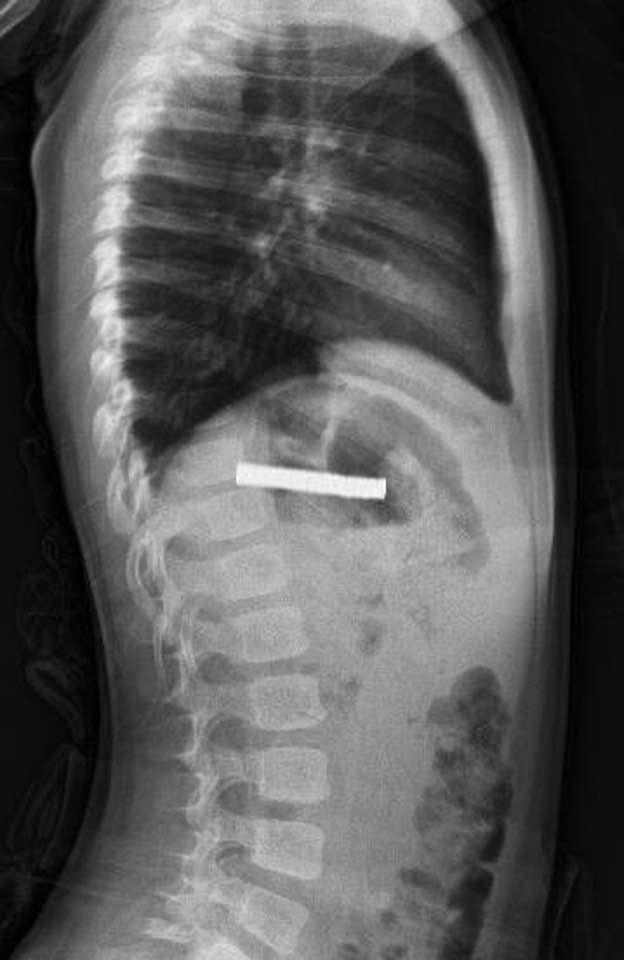

Türkiyənin Elazığ şəhərində 3 yaşlı uşaq 19 ədəd maqnit udub.

AZXEBER.COM Türkiyə mətbuatına istinadən xəbər verir ki, azyaşlı tibbi helikopterlə təcili olaraq xəstəxanaya şatdırılıb.

Qida borusunu bağlayan və uşağın nəfəs almasına maneə yaradan maqnitlər uğurlu əməliyyatla çıxarılıb.